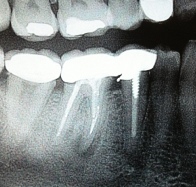

ΑΚΡΟΡΡΙΖΕΚΤΟΜΗ ΚΑΙ ΑΝΑΣΤΡΟΦΗ ΕΜΦΡΑΞΗ ΣΕ ΑΠΟΝΕΥΡΩΜΕΝA  ΔΟΝΤΙA ΚΑΙ ΑΦΑΙΡΕΣΗ ΚΥΣΤΕΩΝ